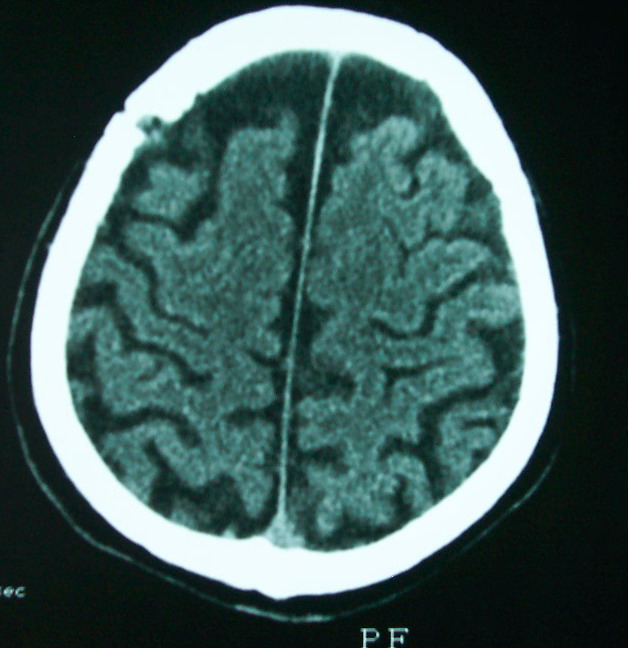

以下是引用余辉在2009-4-15 20:49:00的发言:[br]右侧病灶发生于冠状缝区,但额骨左侧鳞也有病灶,病灶区脑沟裂增宽(有脑萎缩征像,把这个征像放在颅骨病变一起考虑可能有点牵强),是否可能是板障血管畸形所致谢?抑或是嗜酸性肉芽肿或蛛网膜粒压迹那类东西?

以下是引用whzht在2009-4-15 20:57:00的发言:[br]1、额骨改变,考虑蛛网膜粒压迹;[br]2、脑萎缩。